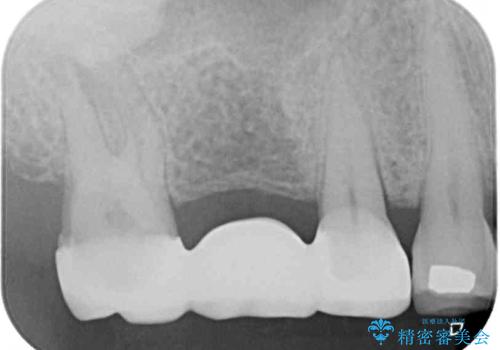

銀歯に隠れていて術前のレントゲンでははっきりと分かりませんでしたが、元々非常に大きなむし歯があったようで、銀歯の中で神経組織が壊死を起こしていました。

速やかに根管治療を行い、無事に痛みを取り除くことができました。